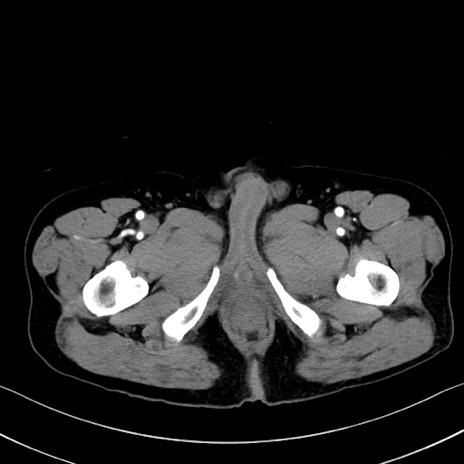

症例35(横断像)

【症例】70歳代 男性

【主訴】腹部膨満、嘔吐

【現病歴】昨日より腹部膨満感出現。本日増悪し、仙痛出現。嘔吐あり、受診。

【既往歴】糖尿病、胆摘後

【身体所見】BP 149/80mmHg、HR 74/min、BT 35.9℃、腹部:膨満、軟、圧痛なし。腸雑音減弱あり。上腹部正中切開瘢痕あり。

【データ】WBC 13500、CRP 1.72